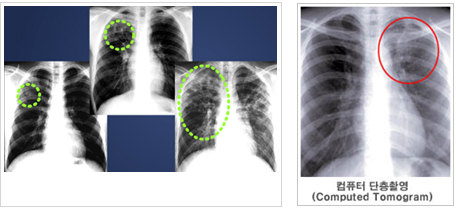

가슴부위의 X선 사진을 촬영하여 폐결핵을 진단하는 방법이지만 단독으로 결핵을 진단하지는 않습니다. 흉부방사선 촬영을 통해 나타나는 음영의 변화를 관찰하여 결핵 발병 여부를 확인할 수 있습니다. 결핵을 앓은 적이 있어서 그 흔적이 남아 있는 사람 중에는 드물게 활동성(병에 걸린 것)인지 또는 비활동성(균은 들어왔었지만 병은 아닌 것)인지 구분이 어려운 예가 있는데, 이 때에는 과거에 찍어 둔 방사선 사진이 있으면 많은 도움이 됩니다. 흉부X선 사진 만으로 진단이 힘든 경우 흉부CT가 유용할 수 있습니다. CT는 오래된 섬유화 병변과 새로운 활동성 병변을 구분하는데 도움을 줍니다. 특히, 공동, 흉곽내 림프절의 비대 또는 염증, 속립성 결핵, 기관지 확장증, 기관지 협착, 흉부질환을 진단하는데 민감도가 높습니다. 다만 흉부방사선 촬영보다 비용이 비싸다는 단점이 있습니다.